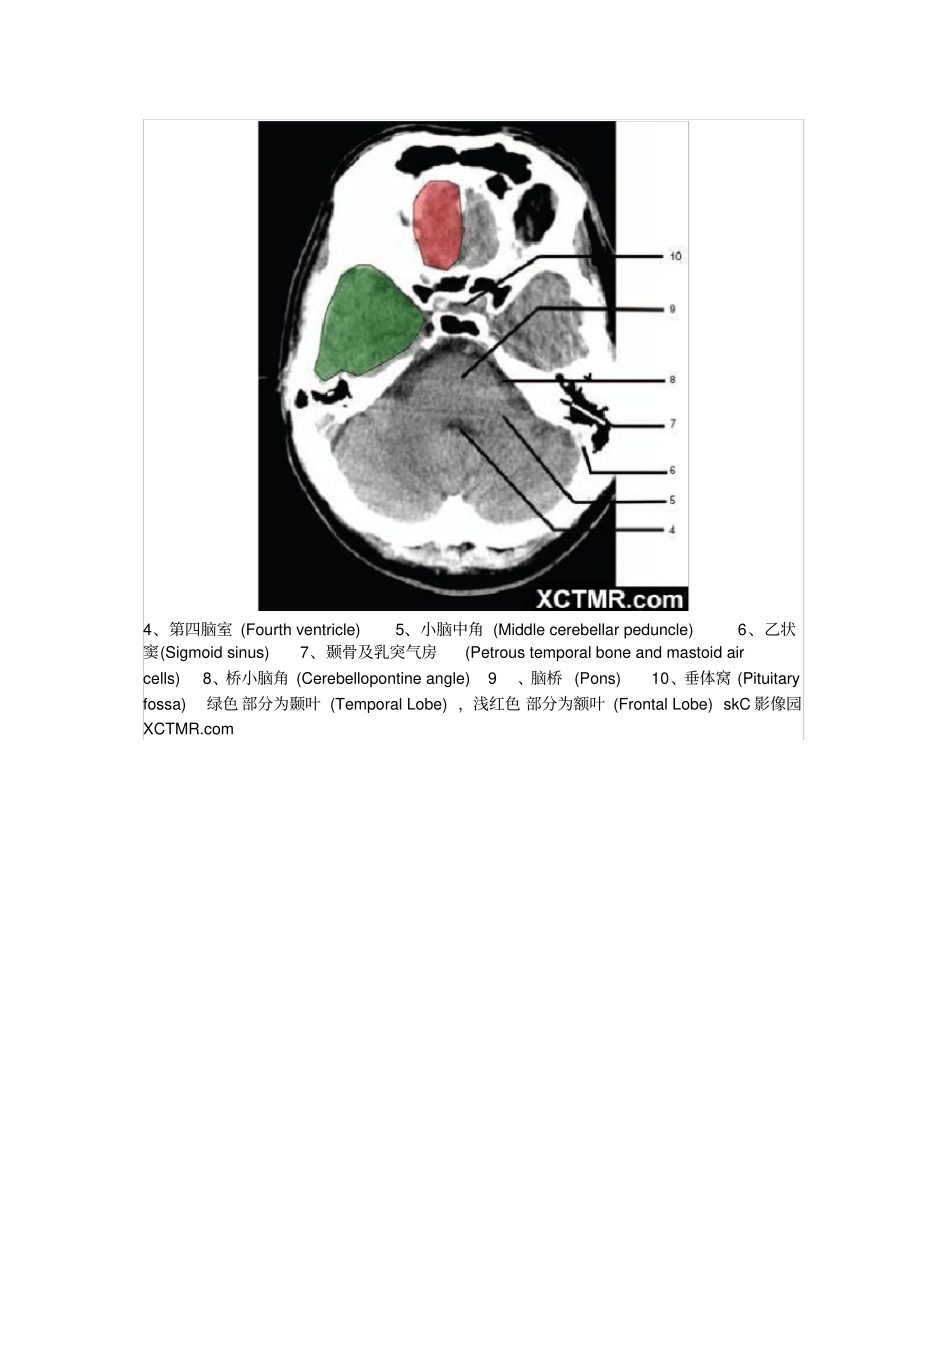

颅脑CT解剖(图文)skC影像园XCTMR.com1、蝶窦(Sphenoidsinus)2、延髓(Medullaoblongata)3、小脑(cerebellum)绿色部分为颞叶(TemporalLobe),浅红色部分为额叶(FrontalLobe)skC影像园XCTMR.comskC影像园XCTMR.comskC影像园XCTMR.com4、第四脑室(Fourthventricle)5、小脑中角(Middlecerebellarpeduncle)6、乙状窦(Sigmoidsinus)7、颞骨及乳突气房(Petroustemporalboneandmastoidaircells)8、桥小脑角(Cerebellopontineangle)9、脑桥(Pons)10、垂体窝(Pituitaryfossa)绿色部分为颞叶(TemporalLobe),浅红色部分为额叶(FrontalLobe)skC影像园XCTMR.comskC影像园XCTMR.com11、小脑蚓部(Cerebellarvermis)12、基底动脉(Basilarartery)13、桥前池(Prepontinecistern)14、鞍背(Dorsumsellae)15、侧脑室颞角(Temporalhornoflateralventricle)绿色部分为颞叶(TemporalLobe),浅红色部分为额叶(FrontalLobe)skC影像园XCTMR.comskC影像园XCTMR.com16、环池(Ambientcistern)17、角间池(Interpeduncularcistern)18、大脑角(Cerebralpeduncle)19、侧裂池(Sylvianfissure)绿色部分为颞叶(TemporalLobe),浅红色部分为额叶(FrontalLobe)skC影像园XCTMR.comskC影像园XCTMR.com20、小脑上池(Thirdventricle)21、侧脑室前角(Frontalhornoflateralventricle)21a、第三脑室(Thirdventricle)绿色部分为颞叶(TemporalLobe),浅红色部分为额叶(FrontalLobe),黄色部分为枕叶(OccipitalLobe)skC影像园XCTMR.comskC影像园XCTMR.com22、尾状核头部(Headofcaudatenucleus)23、岛叶(Insularcortex)24、外囊(Externalcapsule)25、豆状核(Lentiformnucleus)26、丘脑(Thalamus)绿色部分为颞叶(TemporalLobe),浅红色部分为额叶(FrontalLobe),黄色部分为枕叶(OccipitalLobe)skC影像园XCTMR.comskC影像园XCTMR.com27、纵裂(Interhemisphericfissure)28、内囊前肢(Anteriorlimbofinternalcapsule)29、内囊膝部(Genuofinternalcapsule)30、内囊后肢(Posteriorlimbofinternalcapsule)31、侧脑室三角区及脉络丛钙化(Trigoneoflateralventricleandcalcifiedchoroidplexus)32、侧脑室枕角(Occipitalhornoflateralventricle)绿色部分为颞叶(TemporalLobe),浅红色部分为额叶(FrontalLobe),黄色部分为枕叶(OccipitalLobe),褐色部分为顶叶(ParietalLobe)skC影像园XCTMR.comskC影像园XCTMR.com33、侧脑室体部(Bodyoflateralventricle)34、放射冠(Coronaradiata)浅红色部分为额叶(FrontalLobe),黄色部分为枕叶(OccipitalLobe),褐色部分为顶叶(ParietalLobe)skC影像园XCTMR.comskC影像园XCTMR.com35、半卵圆中心(Centrumsemiovale)浅红色部分为额叶(FrontalLobe),黄色部分为枕叶(OccipitalLobe),褐色部分为顶叶(ParietalLobe)额骨(FB—Frontalbone)顶骨(PB—Parietalbone)枕骨(OB—Occipitalbone)skC影像园XCTMR.comskC影像园XCTMR.com36、中央前回(Pre-centralgyrus)37、中央沟(Centralsulcus)38、中央后回(Post-centralgyrus)浅红色部分为额叶(FrontalLobe),褐色部分为顶叶(ParietalLobe)skC影像园XCTMR.comskC影像园XCTMR.com浅红色部分为额叶(FrontalLobe),褐色部分为顶叶(ParietalLobe)skC影像园XCTMR.comskC影像园XCTMR.com浅红色部分为额叶(FrontalLobe),褐色部分为顶叶(ParietalLobe)skC影像园XCTMR.com